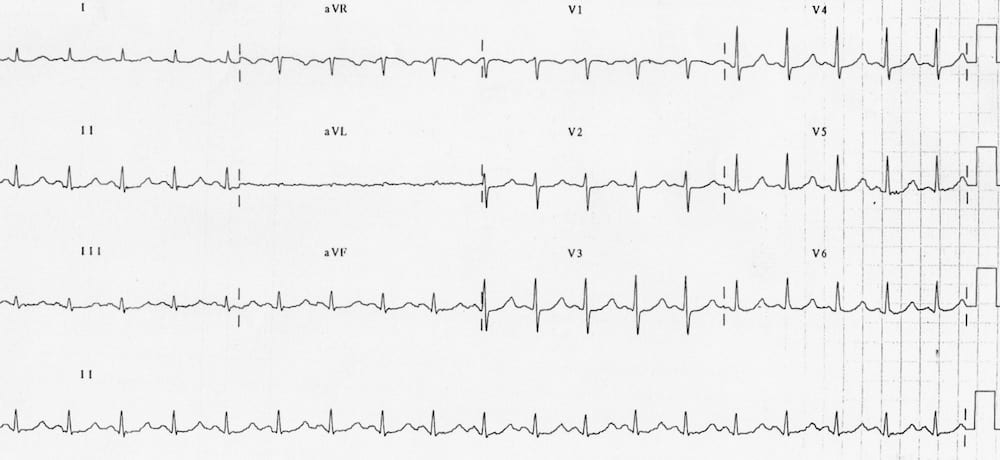

This is an ECG of LVH. Very deep S waves can be seen in V1-V3, with very tall R waves in V4-V6.